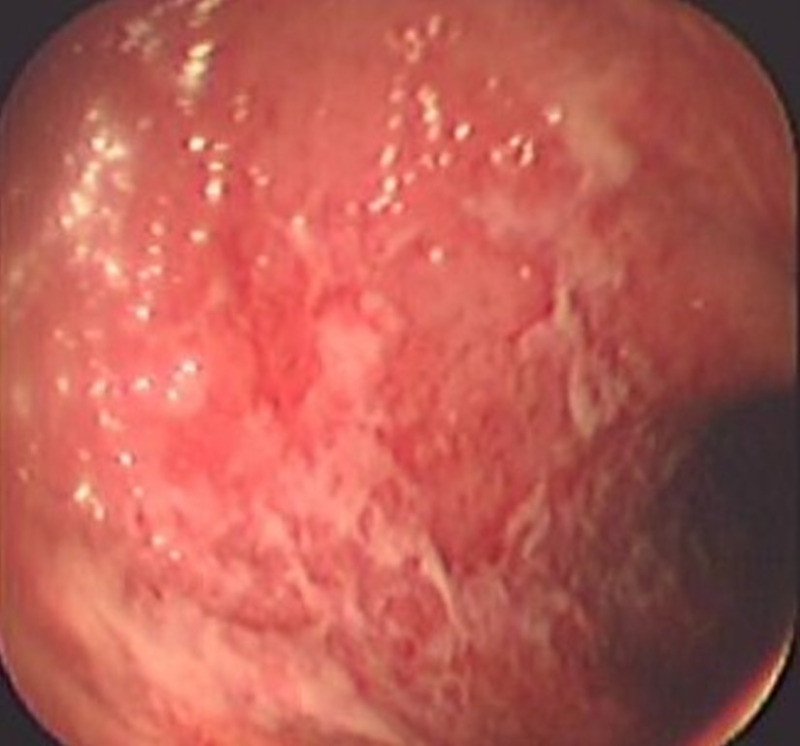

Colitis ulcerosa crónica inespecífica

Envíado por Dr. Carlos Ernesto Arévalo